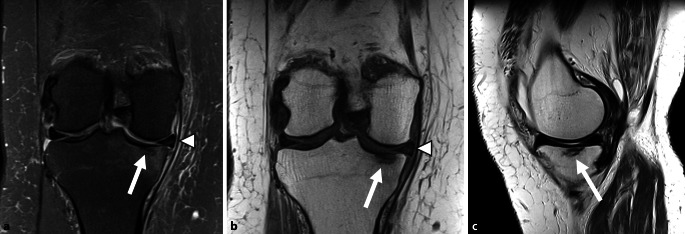

骨髓病变(BML)是在磁共振成像(MRI)上发现的骨髓异常,通常可分为创伤性和非创伤性。本文综述了非创伤性骨髓水肿综合征(BMES)及其影像学评价。MRI仍然是评估BMES的首选方式,特别是使用流体敏感序列,尽管其他序列如Dixon和t1加权成像可以进一步提供帮助。新出现的证据支持双能CT (DECT)作为一种可靠的替代方法,在检测骨髓水肿方面具有高灵敏度和特异性。BMES一词是对短暂性骨质疏松症(TO)和区域性迁移性骨质疏松症(RMO)等病症的统称,主要影响中年个体和孕妇或产后女性的负重骨。膝关节软骨下不全性骨折(SIFK)是BMES的一个关键亚型。这些骨折最常累及股骨内侧髁(MFC),并与危险因素相关,如半月板根撕裂和半月板体挤压。MRI表现通常包括骨髓水肿样信号和软骨下骨折线,并伴有其他特征,如晚期继发性骨坏死。预后指标对患者分层和指导治疗至关重要。低级别或可逆病变通常通过保守治疗解决,而高级别或不可逆病变可能需要手术干预。缺血性坏死是另一种非外伤性BML,不同于BMES,它与全身因素(如类固醇使用或酒精滥用)有关。准确的成像,特别是在早期阶段,对于区分可逆和不可逆病变,促进及时和适当的管理至关重要。

Bone marrow lesions (BML) are abnormalities in the bone marrow identified on magnetic resonance imaging (MRI) and can generally be classified as traumatic or atraumatic. This review focuses on atraumatic bone marrow edema syndromes (BMES) and their imaging evaluation. The MRI remains the modality of choice for assessing BMES, particularly using fluid-sensitive sequences although other sequences such as Dixon and T1-weighted imaging can be of further assistance. Emerging evidence supports dual-energy CT (DECT) as a reliable alternative, with high sensitivity and specificity for detecting bone marrow edema. The term BMES is a collective term for conditions, such as transient osteoporosis (TO) and regional migratory osteoporosis (RMO), predominantly affect weight-bearing bones in middle-aged individuals and pregnant or postpartum females. Subchondral insufficiency fractures of the knee (SIFK) are a key subset of BMES. These fractures most commonly involve the medial femoral condyle (MFC) and are associated with risk factors, such as meniscal root tears and extrusion of the meniscal body. The MRI findings typically include bone marrow edema-like signals and subchondral fracture lines, with additional features, such as secondary osteonecrosis in advanced cases. Prognostic indicators are crucial for stratifying patients and guiding management. Low-grade or reversible lesions often resolve with conservative treatment, whereas high-grade or irreversible lesions may require surgical intervention.Avascular necrosis, another atraumatic BML entity, differs from BMES by its association with systemic factors, such as steroid use or alcohol abuse. Accurate imaging, particularly in the early stages, is vital to distinguish between reversible and irreversible lesions, facilitating timely and appropriate management.